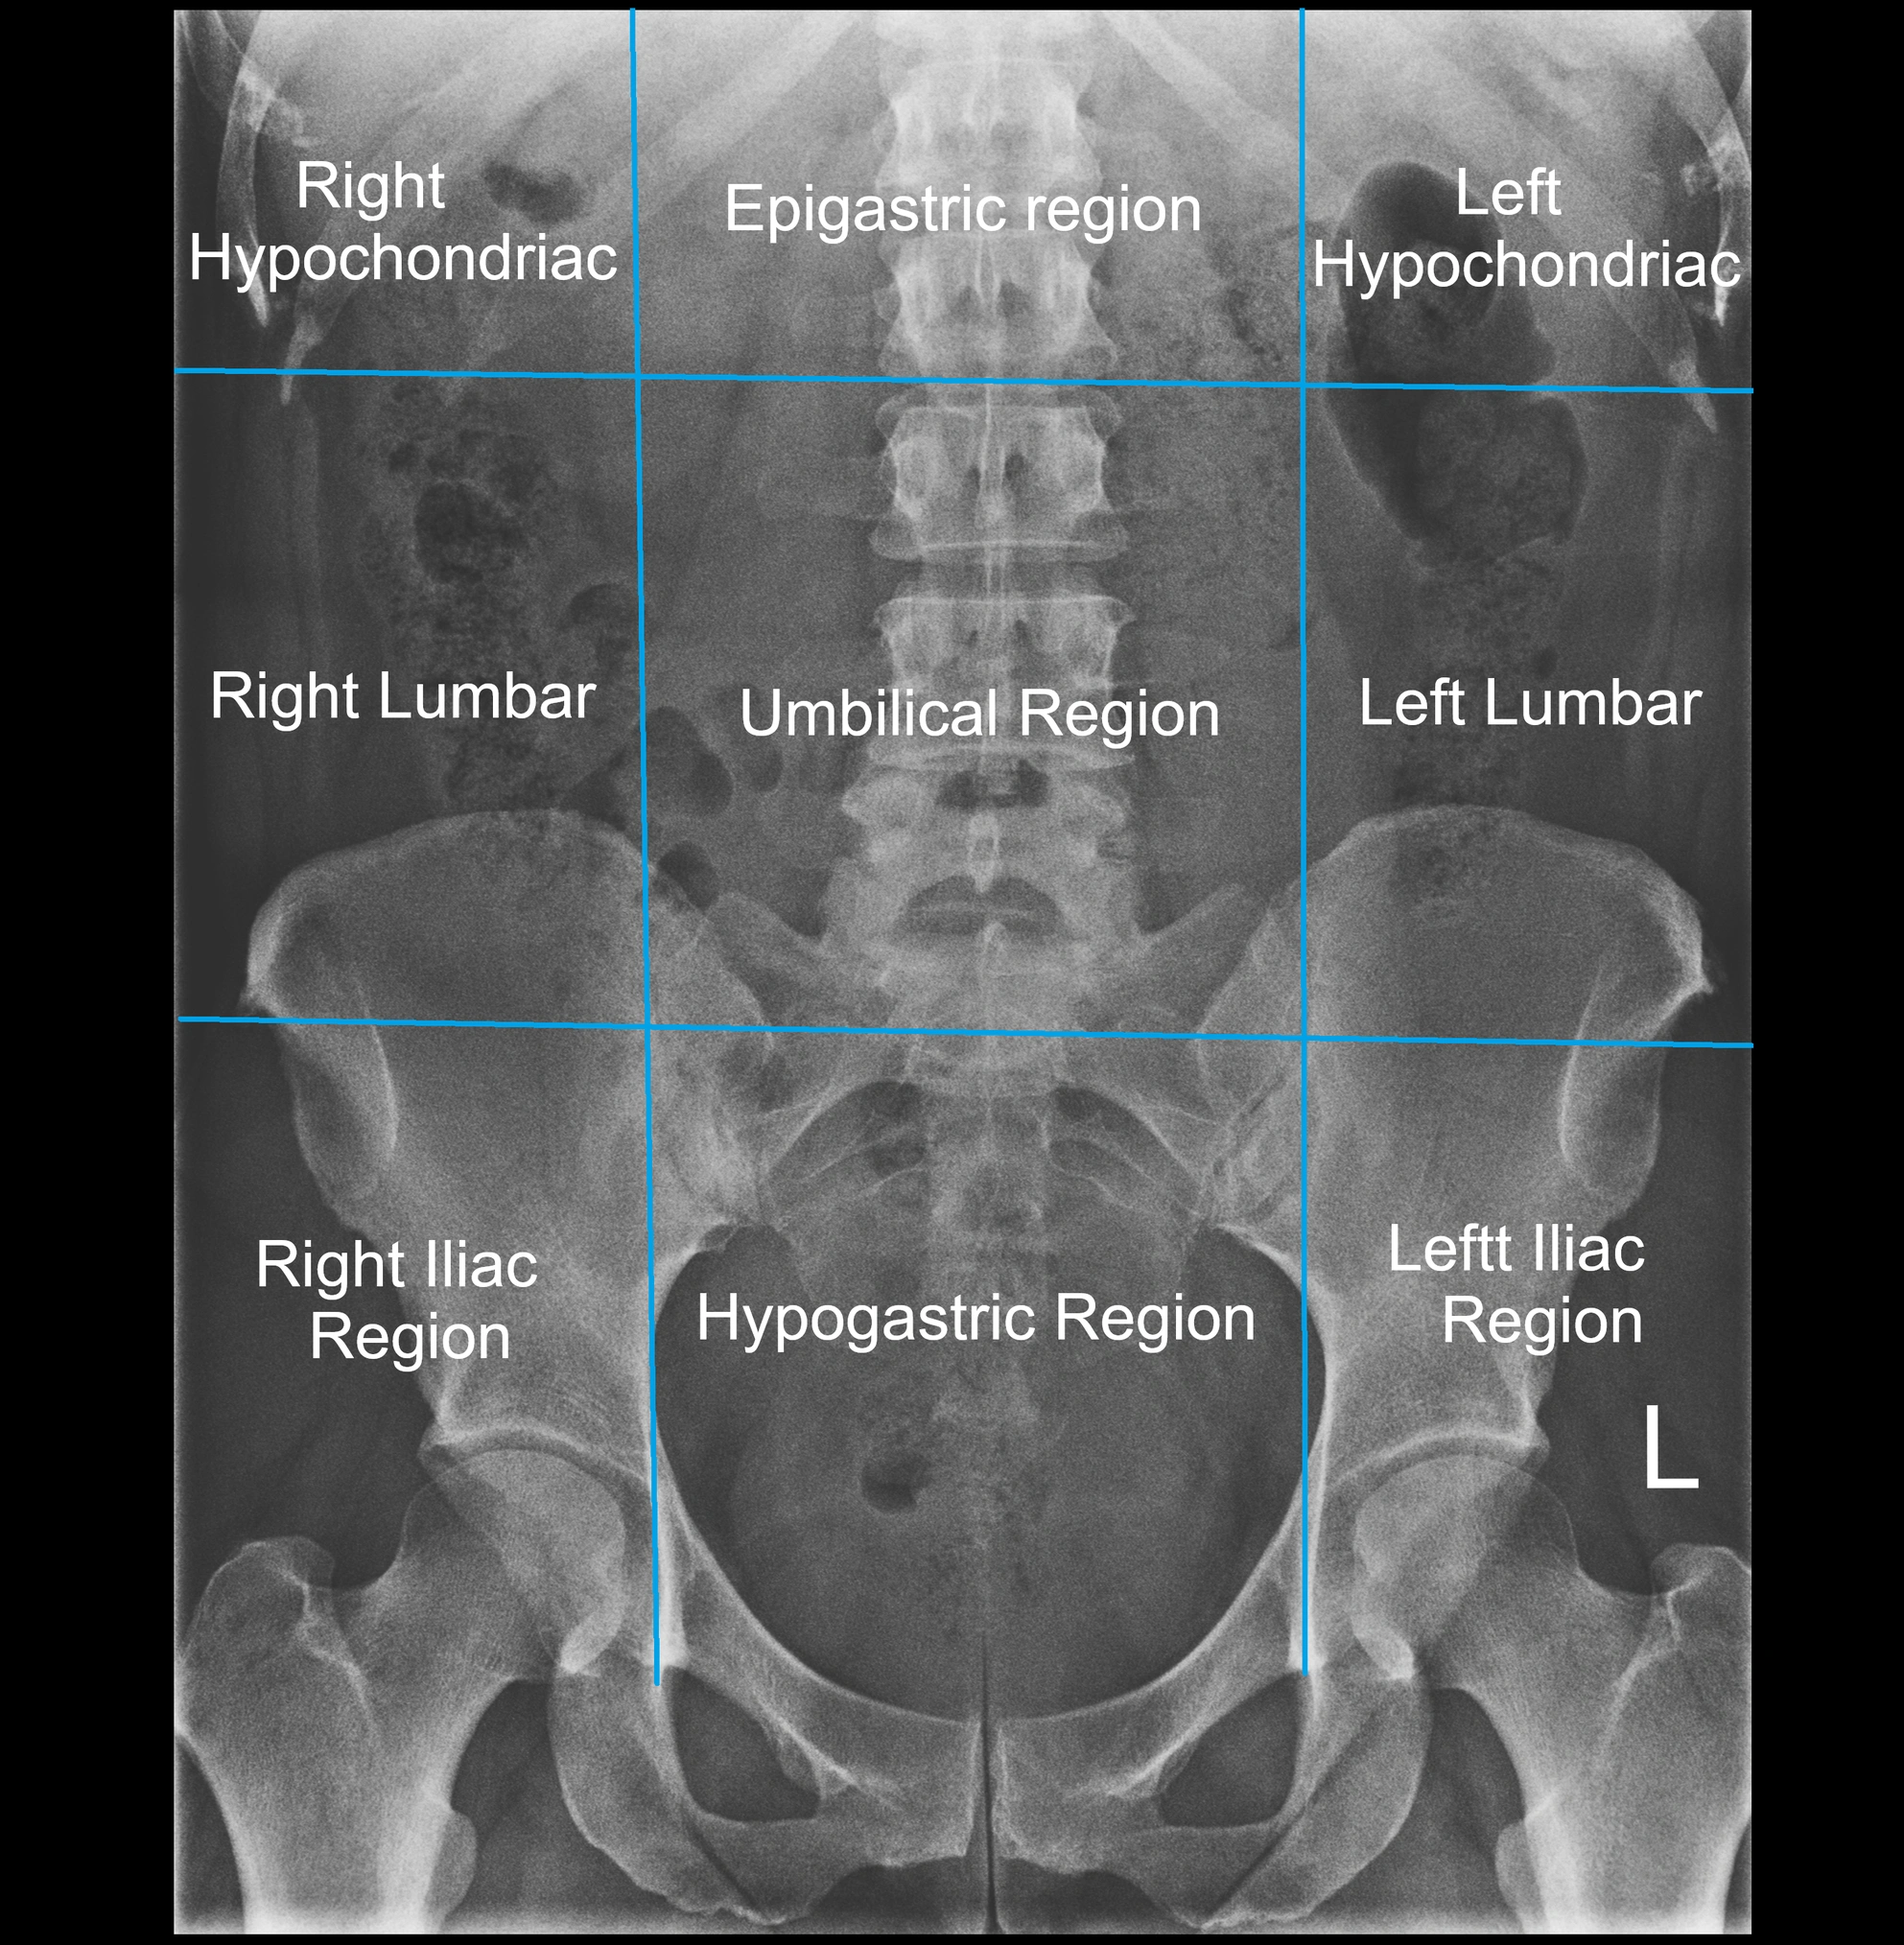

• Acts as a radiological landmark in lumbar spine imaging

• Important in differentiating normal anatomy from fractures, accessory ossicles, or pathology